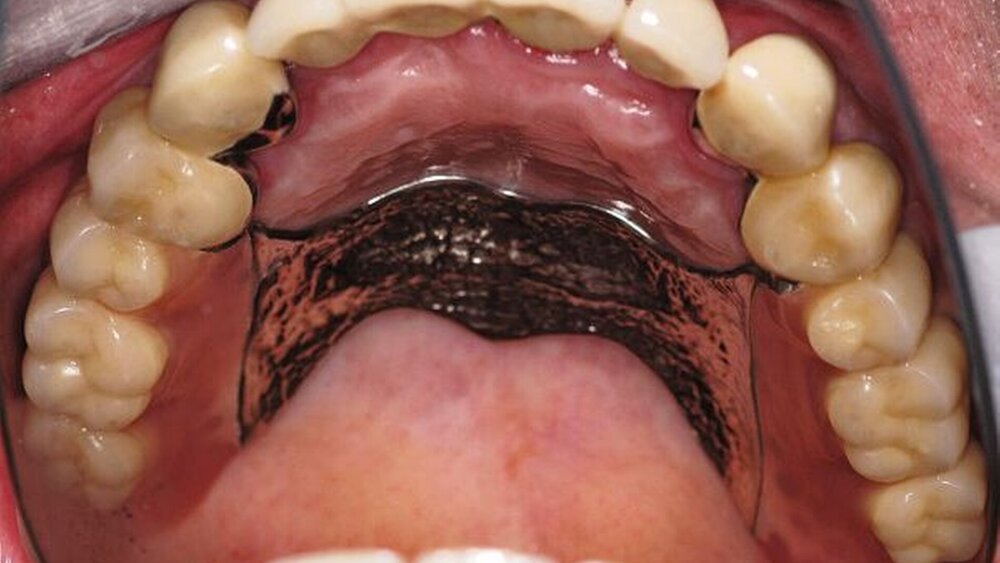

Im Rahmen der intraoralen Befunderhebung wurde festgestellt, dass die Gingiva insgesamt gerötet und ödematös war. Die Messung der Taschentiefe ergab einen durchschnittlichen Wert von fünf mm. Der ermittelte PSI (in Bezug auf die Sechstanten) ergab die Werte 4, 2, 4, 3, 2, 2. Pusaustritt konnte in regio 17 und in regio 27 festgestellt werden, so dass der Erhalt dieser Zähne fraglich war. Im Oberkiefer lag ein prothetisch versorgtes Lückengebiss der Kennedy-Klasse III2 vor. Die Zähne 18, 16, 15, 11, 25, 26 und 28 fehlten. Die prothetische Versorgung bestand aus einer Brücke 17 bis 14 zum Ersatz von 16 und 15, einer Brücke 13 bis 23 zum Ersatz von 11 und einer Brücke 24 bis 27 zum Ersatz von 25 und 26. Sämtliche Brückenanker wiesen Randundichtigkeiten und Sekundärkariesbildung auf. An 21 konnte eine großflächige Keramikabplatzung festgestellt werden. 17 und 27 reagierten im Perkussionstest stark positiv. Im Rahmen einer Sensibilitätsprüfung mittels CO2-Schnee reagierten die Zähne 17, 22 und 27 negativ. Im Unterkiefer lag ein Gebiss der Kennedy-Klasse II3 vor. Die Zähne 38, 36, 34, 44, 45, 47 und 48 fehlten. Die Zähne 37, 42, 46 waren mit Füllungen versorgt, die erhebliche Undichtigkeiten aufwiesen. 46 reagierte im Kältetest negativ. Alle Unterkieferzähne wiesen starke Attritionen auf. Diese Zähne 33 bis 43 sowie 37 und 35 reagierten im Kältetest stark schmerzhaft (Abbildungen 4, 5).